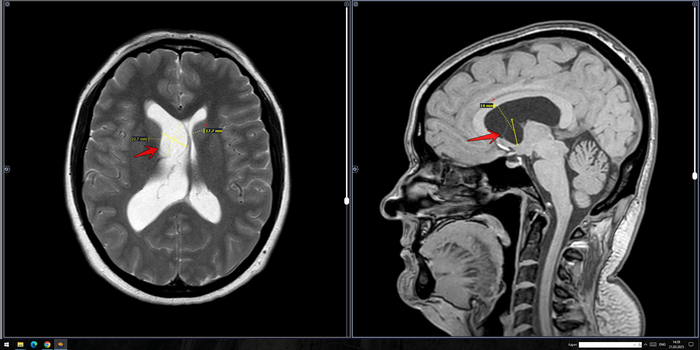

В расширенном турецком седле определяется солидное объемное образование неоднородно повышенного МР-сигнала на Т2 ВИ, размерами до 30 х 25 х 19 мм, неоднородно копит контраст. Образование распространяется в область кавернозных синусов по ходу С5 С6 сегментов внутренних сонных артерий, муфтообразно охватывая их до 70% окружности справа и до 50% окружности слева. Внутренние сонные артерии на уровне образования не сужены. Образование интимно прилежит к задним базальным отделам прямых извилин и зрительному перекресту, больше справа, без его оттеснения. Воронка гипофиза утолщена, отклонена вправо.На этом фоне нормальная структура гипофиза четко не определяется, вероятно, оттеснена вправо и кзади.

Заключение: МР- картина образования гипофиза, соответствует макроаденоме средних размеров с супра- и латероселлярным характером роста. Рек-но: конс. нейрохирурга.